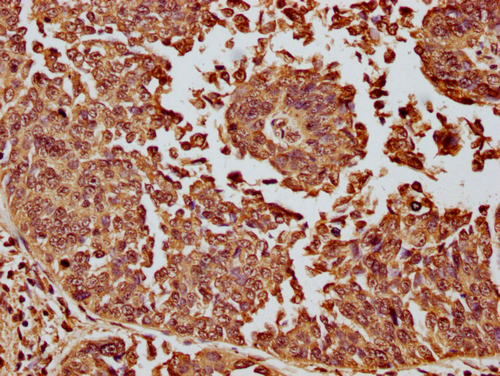

IHC image of CSB-PA010087OA11nme1HU diluted at 1:10 and staining in paraffin-embedded human cervical cancer performed on a Leica BondTM system. After dewaxing and hydration, antigen retrieval was mediated by high pressure in a citrate buffer (pH 6.0). Section was blocked with 10% normal goat serum 30min at RT. Then primary antibody (1% BSA) was incubated at 4°C overnight. The primary is detected by a biotinylated secondary antibody and visualized using an HRP conjugated SP system.

IHC image of CSB-PA010087OA11nme1HU diluted at 1:10 and staining in paraffin-embedded human kidney tissue performed on a Leica BondTM system. After dewaxing and hydration, antigen retrieval was mediated by high pressure in a citrate buffer (pH 6.0). Section was blocked with 10% normal goat serum 30min at RT. Then primary antibody (1% BSA) was incubated at 4°C overnight. The primary is detected by a biotinylated secondary antibody and visualized using an HRP conjugated SP system.